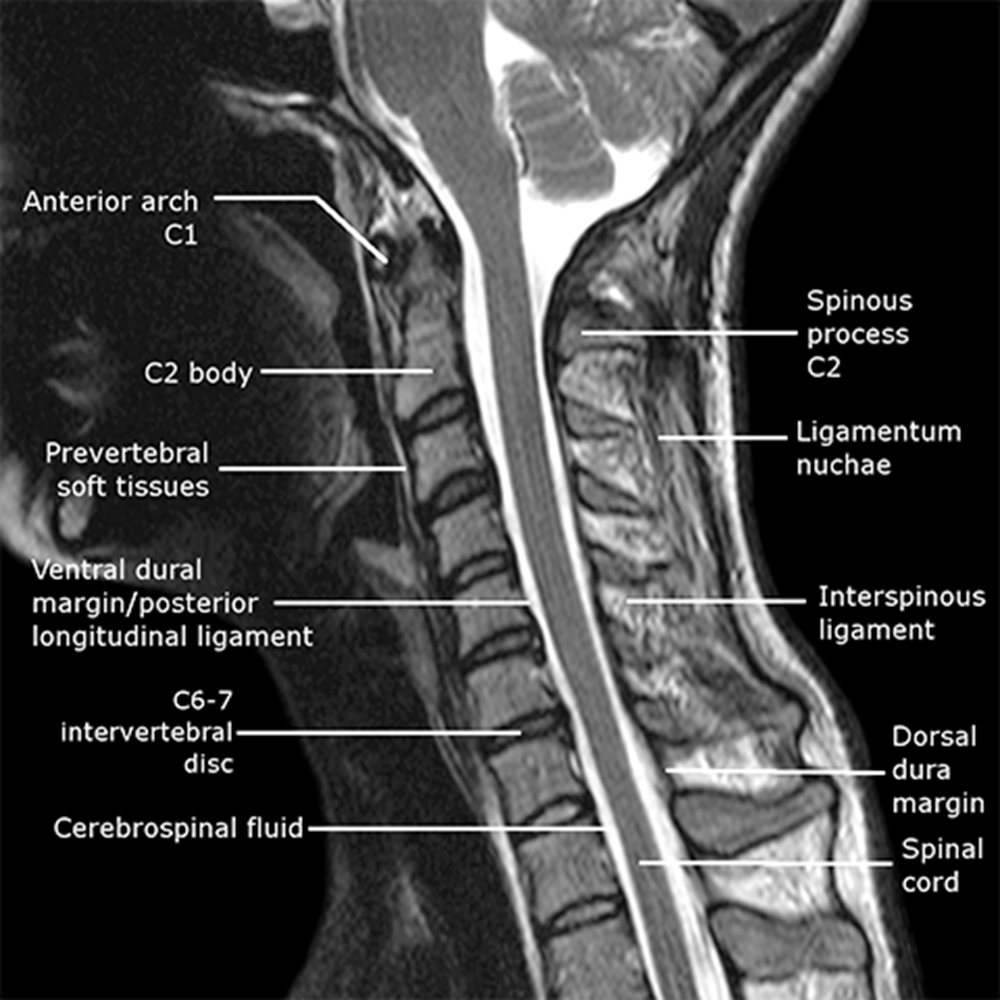

___ mater directly connected to spinal cord

Most peripheral is ____ mater

Vertebral body is ______ to spinal cord

Cervical cord landmarks